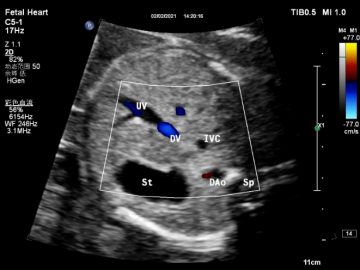

| 观察内容 | 1、2D:腹主动脉位于脊柱的左前方,下腔静脉位于脊柱的右前方,下腔静脉位于腹主动脉的右前方,胃泡位于左上腹腔,正常脐静脉位于腹中略偏左。 |

| 2、CDFI:显示脐静脉与下腔静脉之间的一段明亮血流,即静脉导管。 | |

| (图1、2) | |

| 图1 胎儿胃泡水平腹部横切面二维显像 | 图2 胎儿胃泡水平腹部横切面彩色多普勒显像 |

注:UV:脐静脉;St:胃泡;DAo:降主动脉(腹主动脉);Sp:脊柱;IVC:下腔静脉;DV:静脉导管

图3 胎儿静脉导管血流频谱